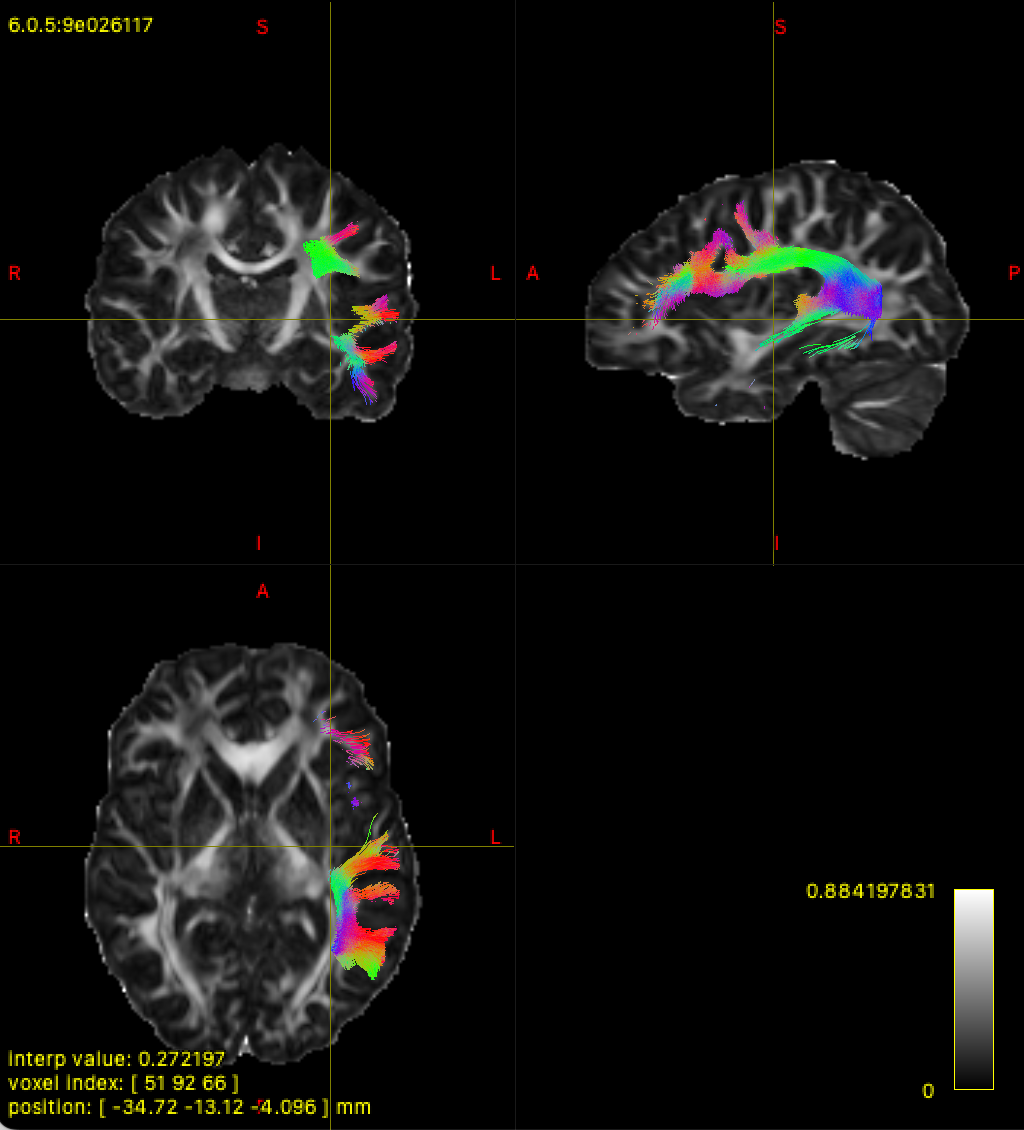

I noticed that in the master branch, compared to 2.3 that I used previously, tract files (I have tested on both --tracking_format tck and trk) are no longer in DWI space. When I load the tck/trk file in MRView/FSLeyes, the tract file is out of bounds of the DWI reference image (in this case, I used FA).

In version 2.3, as seen below with the left AF, trk and tck map onto the image (top is trk in FSLeyes, bottom is tck in MRView). However, it is worth noting that the left AF appears on the wrong hemisphere for the trk file, while the tck file is correct: